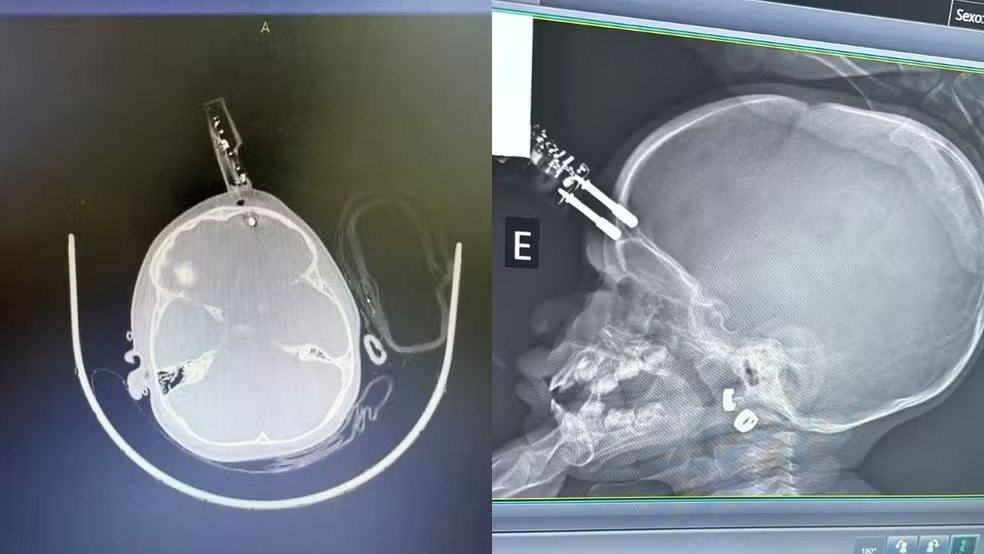

Uma menina de 1 ano precisou passar por uma cirurgia de emergência após cair da cama e ter um carregador de celular cravado na testa, em Divinópolis. Segundo o neurocirurgião responsável pelo atendimento, a criança segue internada, sem sinais de sequelas neurológicas até o momento.

O acidente ocorreu quando a mãe teria se ausentado por alguns instantes. A criança segurava o carregador ao cair, fazendo com que o objeto perfurasse a região frontal do crânio, próximo ao olho. Ela foi imediatamente levada ao bloco cirúrgico, onde o dispositivo foi retirado, a área limpa e reconstruída.

O médico alertou que o principal risco em casos assim é a lesão cerebral, já que o objeto atravessou o osso e atingiu o cérebro, podendo causar hemorragia. A perfuração também aumenta o risco de infecção, como meningite. A criança recebe antibiótico profilático e seguirá em acompanhamento neurológico devido à possibilidade de complicações futuras.